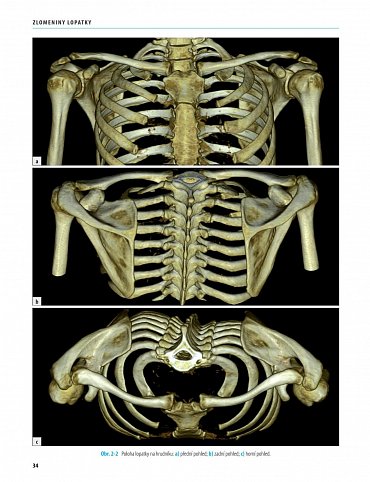

První monografie věnovaná zlomeninám lopatky v domácí i světové literatuře. Kniha vysvětluje obecné principy diagnostiky a terapie zlomenin lopatky doprovázené podrobným rozborem 519 zlomenin lopatky u dospělých, z toho 150 operovaných případů, 39 zlomenin u dětí a dospívajících.